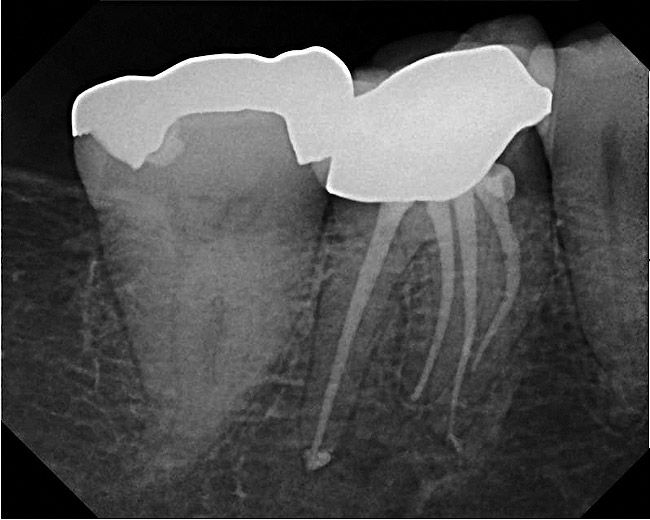

A 42-year-old woman presents for emergency treatment with a chief complaint of severe pain over the past 2 days in her upper jaw. The patient attributes the pain to tooth No. 3, as it received endodontic therapy 2 years ago (Figure 1). She complains of severe (pain score of 9/10), dull, throbbing pain in the right side of the face, jaws, and cheek that radiates into the temple with episodes of acute sharp pain, which is more severe at night, and appears to be stemming from the maxillary right molar (tooth No. 3). The patient has been awakened with pain over the past couple of nights and takes 600 mg of ibuprofen for relief. The patient also complains of a history of cold sensitivity from that tooth over the past couple of months and a history of low-grade chewing pain ever since the root canal. The past dental history is significant for a recent prophylaxis and fluoride treatment within the past month, and two fillings in the maxillary left side (teeth Nos. 12 and 14), and a crown in tooth No. 30 within the past 3 months (Figure 2). The patient’s medical history is insignificant, with no allergies reported. Extraoral tests are insignificant for objective findings. Intraoral tests show that tooth No. 3 is sensitive to percussion (3/10) and the radiograph shows a localized periapical radiolucency associated with the mesiobuccal (MB) root of this tooth.

Figure 1  Preoperative view of tooth No. 3.

Figure 1